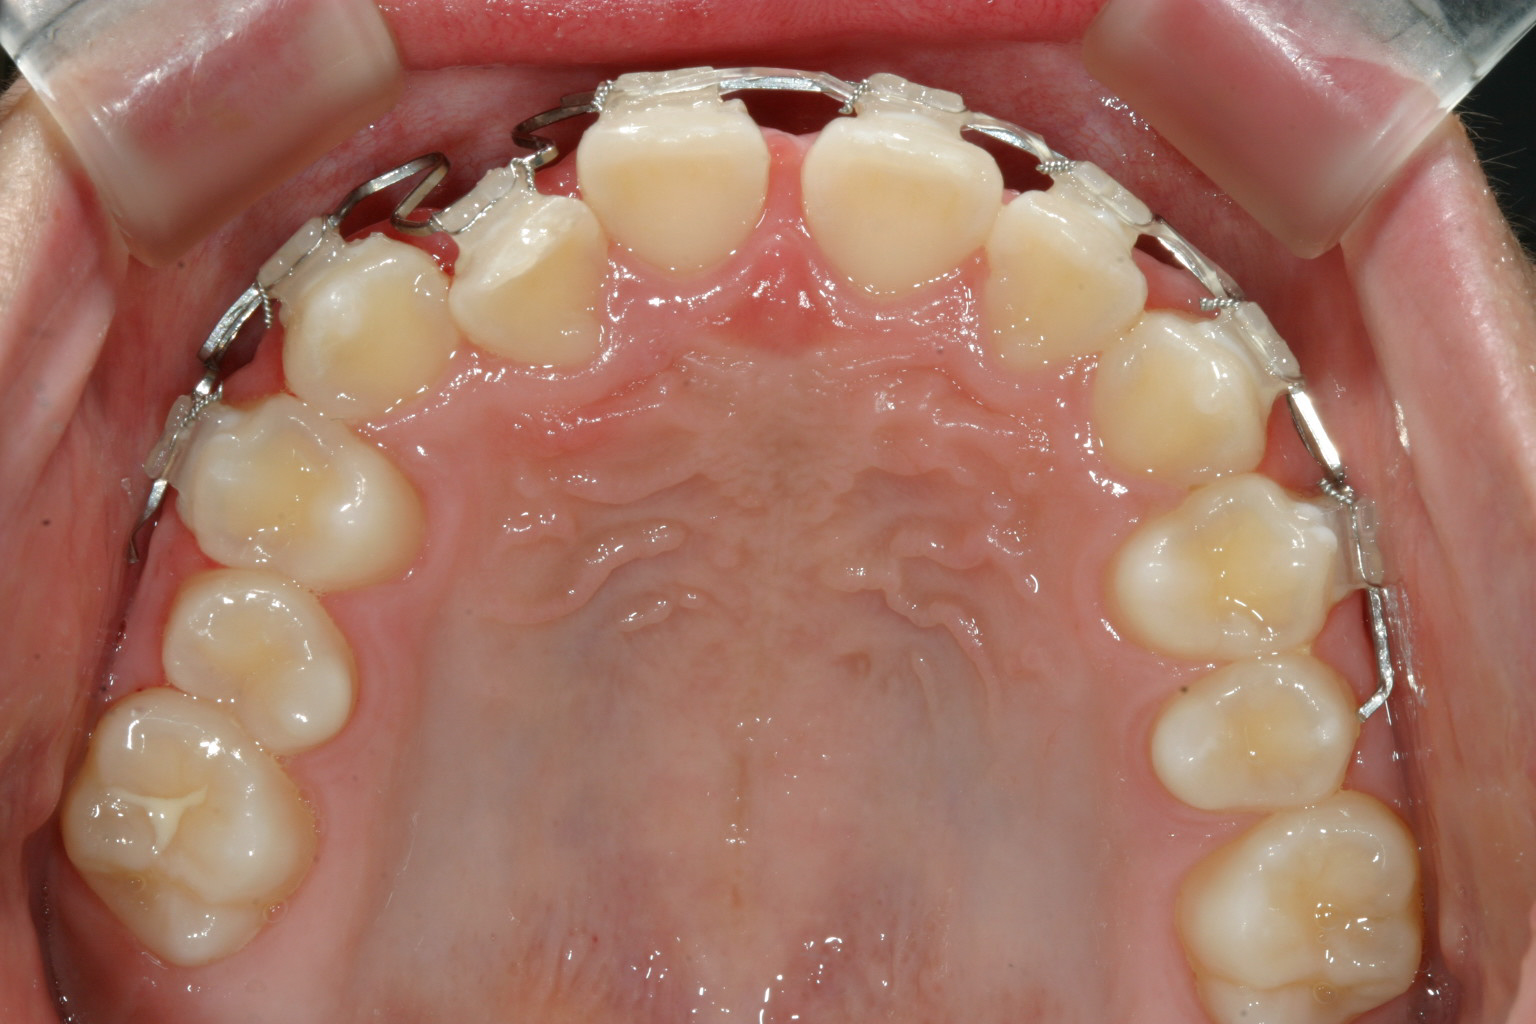

ワイヤー張って2ヵ月です。

初診より4ヵ月で終了です。

初診より僅か4カ月で受け口終了しました。

まだ10歳の子供さんの為顎の骨も柔らかくマルチループワイヤーで短期間で治療する方法を試みました。

今回の場合はマルチループワイヤーを使用することにより短期間で終了致しました結果お母さまにも通院回数も少なくて喜ばれました。